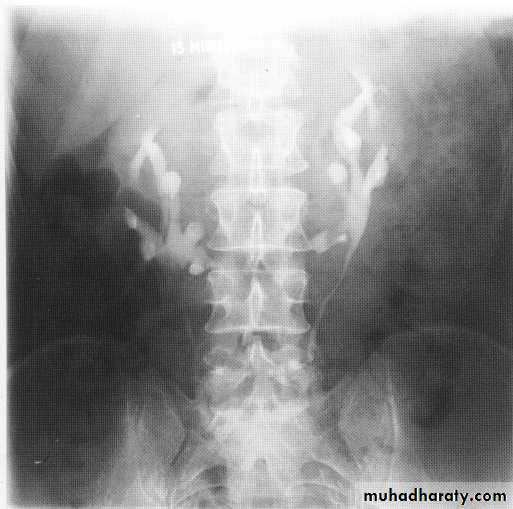

Polycystic kidneys

I n autosomal recessive polycystic disease of the kidneys (ARPCK) the renal parenchyma is replaced by numerous tiny (1-8 mm) cystsOn IVU there is a striated nephrogram thought to be due to contrast lying in the minority of preserved functioning tubules next to dilated non-opacified diseased tubules.

Polycytic disease

In autosomal dominant polycystic disease of the kidneys(ADPCK) numerous cysts of varying size, often becomingextremely large, develop within the kidneys, gradually replacingnormal renal parenchyma and ultimately producing renal failure. It usually presents between 20 and 39 years of age